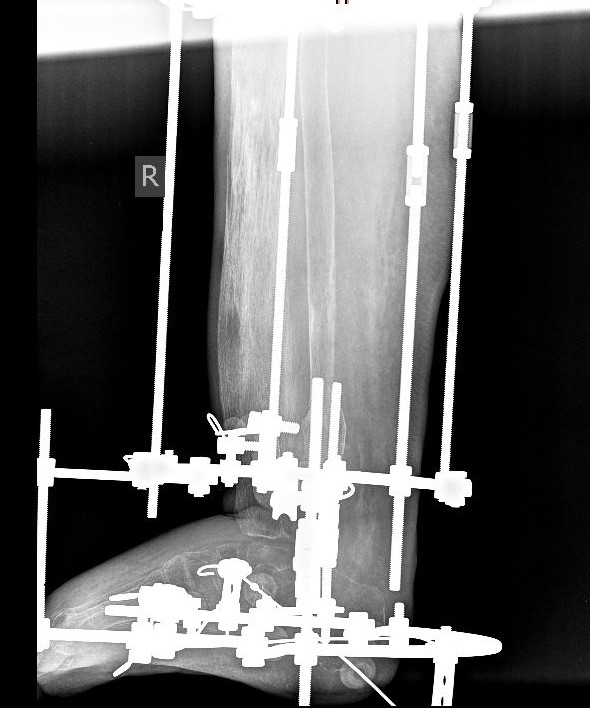

«Мы выполнили реостеосинтез аппаратом Илизарова голени и стопы. Добиваемся полного сращения большеберцовой и таранной костей, чтобы получить артродез голеностопного сустава, минуя трофические проблемы», — рассказал суть оперативного лечения заведующий отделением №3 Центра Илизарова Виталий Нарицын.

После операции пациентка начала наступать на ногу и ходить. Врачи Центра Илизарова говорят, что в настоящее время костная ткань не готова к дальнейшей реконструкции, выраженный остеопороз настолько, что для проведения спиц не требуется силовое оборудование. Необходимо, чтобы пациентка начала активно ходить, в таком случае костная ткань обретет свою прочность и укрепит структуру.